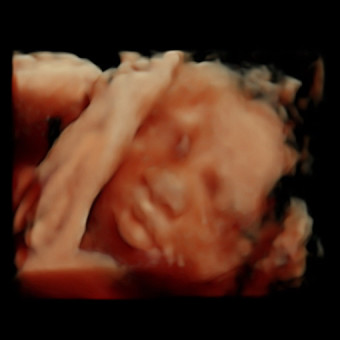

Mandy’s Baby Sprinkle

Mandy Seabrook

We’re so excited to be welcoming another little love to our family! Your love and support mean the world, thank you for helping us prepare for baby’s arrival.